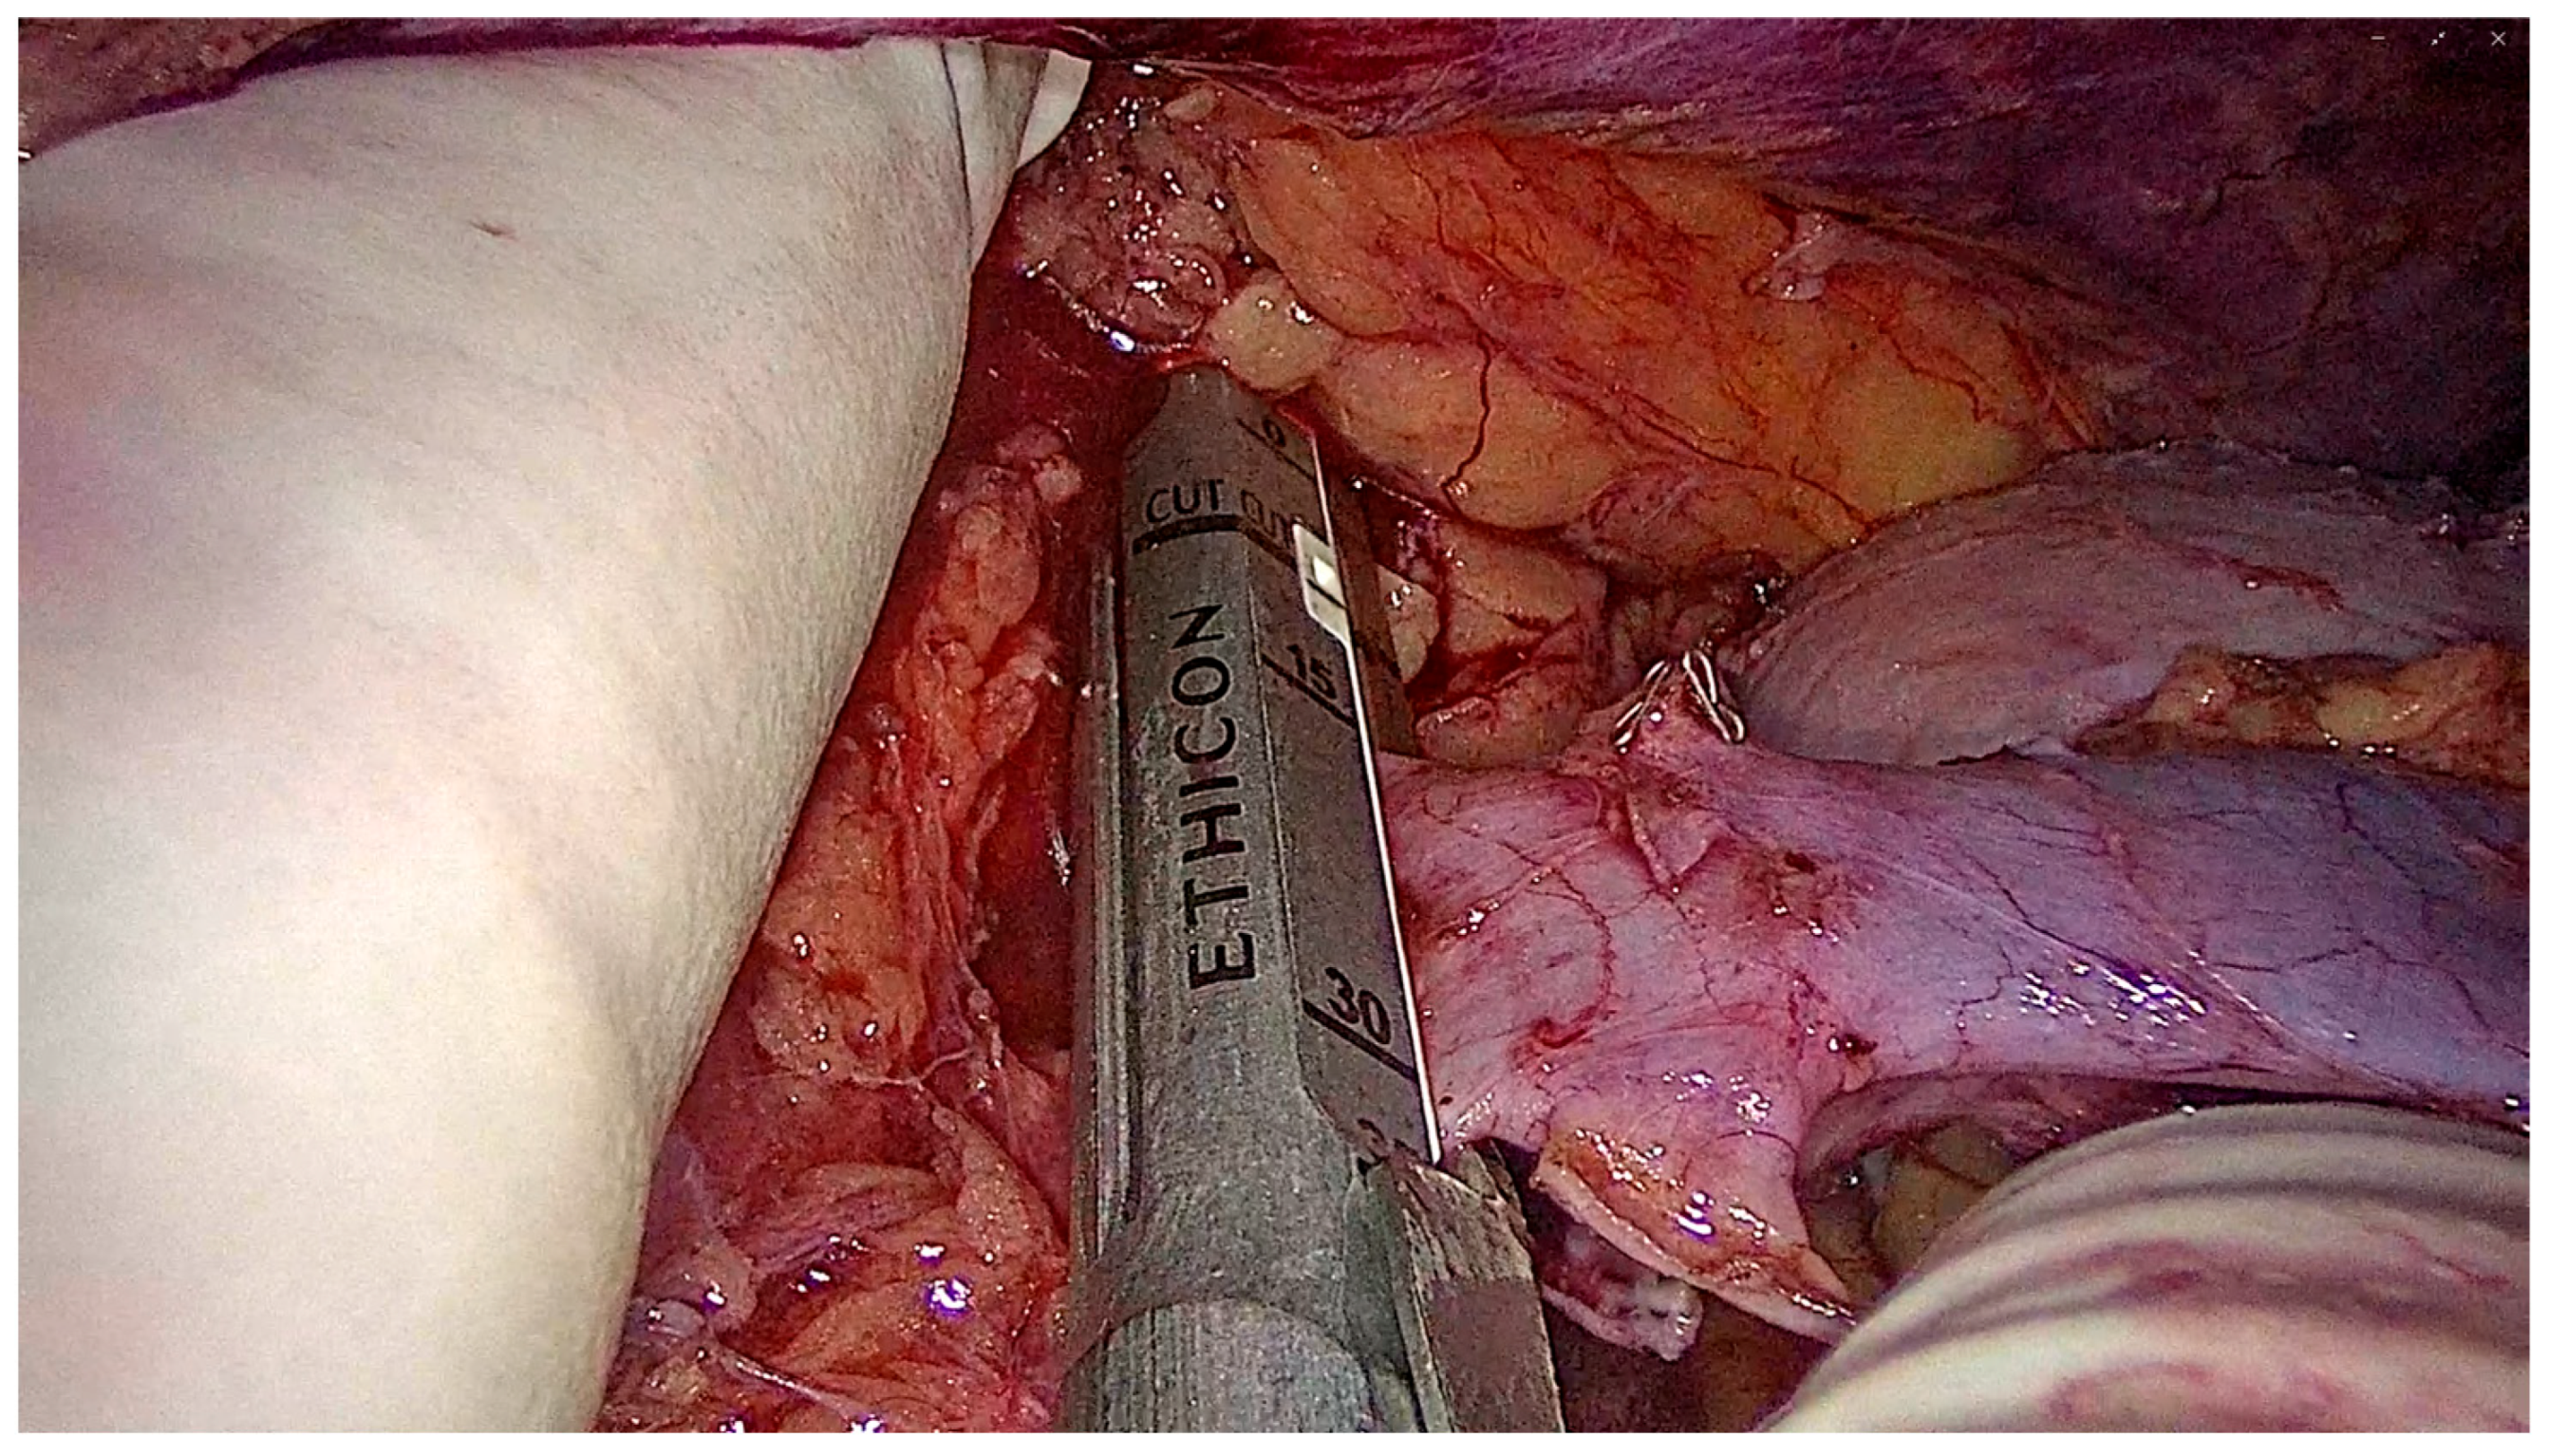

2.6.4. Graft Procurement and Extraction

2.6.5. Closure